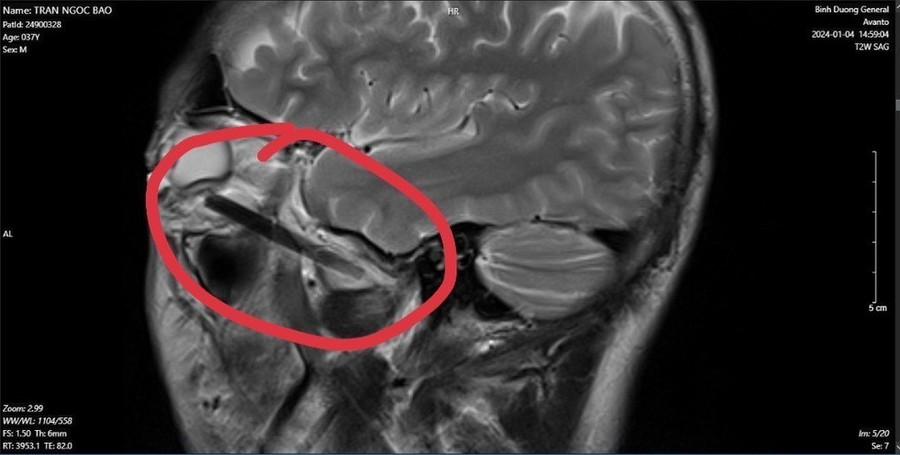

| Hình ảnh dị vật trong mắt người đàn ông ở tỉnh Bình Dương. (Ảnh: TTXVN phát) |

Các bác sỹ phát hiện một phần chiếc đũa dài khoảng 6cm, nằm sâu trong hốc mắt người đàn ông này.

Sau khi phẫu thuật, các bác sỹ đã lấy được dị vật trong hốc mắt của người bệnh là đầu đũa gỗ bị gãy với chiều dài gần 6cm.

Theo các bác sỹ, dị vật hốc mắt là bệnh ít gặp, dị vật hốc mắt cần được lấy và điều trị kịp thời tránh viêm tổ chức hốc mắt và viêm thị thần kinh gây mất thị lực. May mắn đối với người bệnh là khi vào viện chỉ mới bị viêm tổ chức hốc mắt, chưa dẫn đến viêm thị thần kinh và được các bác sỹ chẩn đoán, điều trị kịp thời. Đây là một trường hợp mắc dị vật ở mắt phức tạp và khó xử lý vì dị vật nằm khá sâu, phẫu trường hẹp.